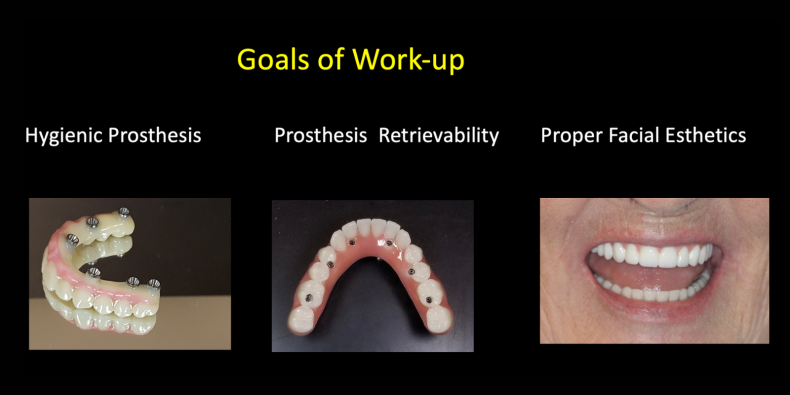

We examine you, obtain radiographs including a CT scan, digital scan of your teeth, and analyze your facial esthetics with our FaceHunter. We provide you with the cost of our treatment.

Our doctors work with our lab technicians to analyze your smile and functional needs. We pre-plan a new set of teeth, and reverse engineer the precise positions your implants need to be in for your new teeth. From this we make surgical guides – comprised of three or four components that get attached to your bone and stack together. They are used while you are asleep to accurately position your implants. They also guide the digital scanning used to manufacture your custom teeth.

Factors affecting their success are proper placement for hygiene, surgical execution and planning. Importantly, is prosthesis designed, so it is easy to clean at home.